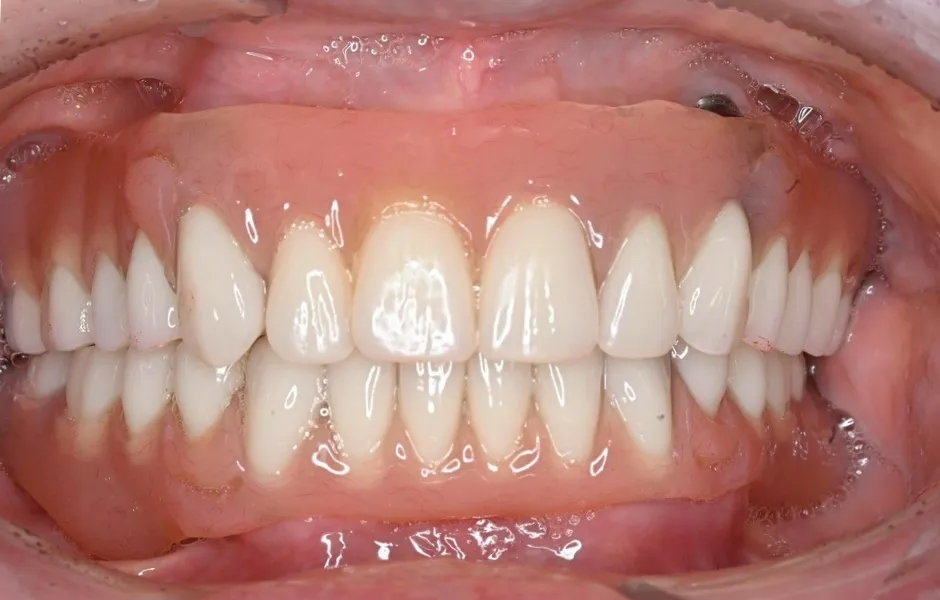

インプラント治療

失った歯を補う方法の1つで、インプラントが歯根の代わりを果たすことで天然歯に近い噛み心地を再現します。当院ではサージカルガイドを使用することで、より精密な埋入を可能とし、術後の痛みや腫れを軽減しています。機能性だけでなく審美性も回復します。

オールオン4・6

歯をすべて失っている方にインプラントを4~6本埋入して、連結した人工歯を支える治療法です。手術回数と埋入数が少ないので、患者さまの体への負担と費用を軽減できます。

全顎治療・咬合治療

(歯がボロボロ)虫歯や歯周病が悪化して、歯を失っている・ボロボロのまま放置すると、機能性と審美性に影響がでます。お口のトラブルを改善できるよう、さまざまな治療をご提案します。